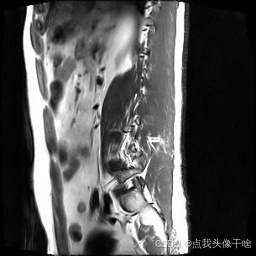

想象一下,你给AI看一张脊椎的核磁共振(MRI)照片,它就能像经验丰富的医生一样,把照片里每一块骨头、每一节椎间盘都给你清清楚楚地标记出来。这个系统干的就是这个酷炫的事儿!

- 原图:就是一张张脊椎的MRI扫描图。

- 标准答案:对应每张原图,都有一张标注好的“答案图”,图中已经把不同部位(比如不同的椎体、椎间盘)用不同的颜色或灰度标好了。